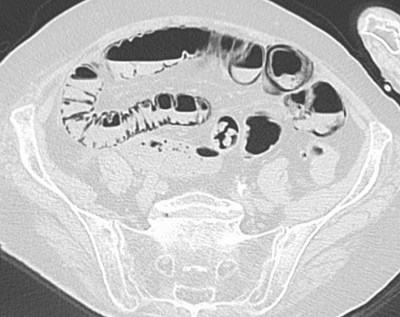

- Picture: CT (axial view)

- Pneumatosis Intestinalis

- Invasion of gas-producing bacteria into the intestinal walls / dissection of intraluminal gas due to increased pressure in the GI tract.